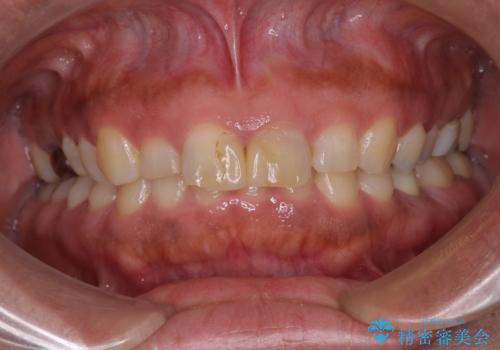

- 前歯の形と色を気にして来院された患者様です。

虫歯で神経を取り除いたことによる変色や充填物の着色などが認められたため、オールセラミッククラウンにて補綴することとしました。

また、咬耗により周囲の歯がすり減ったことで、前歯2本のみが長く見えていたため、周囲に長さを合わせることとしました。